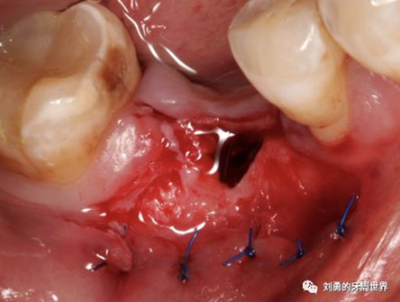

比如下圖:

但是該方法有個弊端,那就是受區(qū)沒有骨膜了,齦瓣的血供會變差,有人提出來了改良的方法,就是保留骨膜,但是為了減少骨膜上纖維的移動性,對骨膜進(jìn)行垂直向的全厚層切透,減少骨膜的動度,這就是垂直骨開裂的改良方法,如下圖:

還有人提出來的改良方法是在半厚瓣骨膜床的根尖區(qū)域做全厚層切口,離斷來自根向的肌肉纖維或系帶的牽拉,該方法稱之為骨膜分離的方法,如下圖: